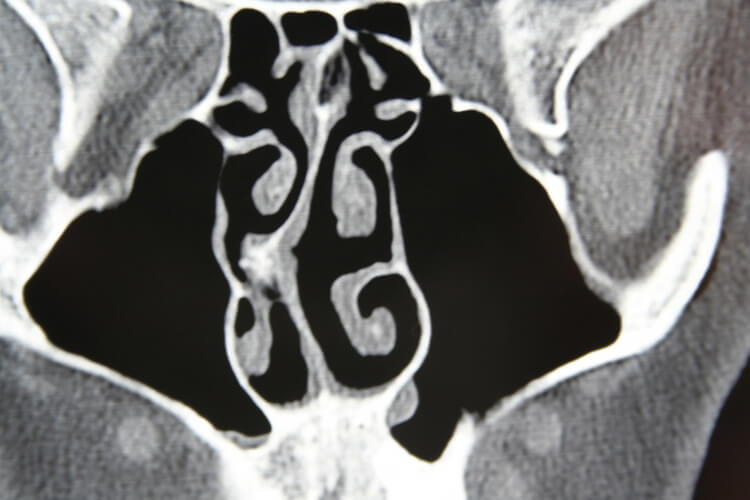

The septum is the wall that separates the left and right nasal cavity. If nasal obstruction caused from a septal deviation is your primary issue, then a septoplasty can offer definitive treatment of your breathing problems. Typically, nasal obstruction caused from a deviated septum is initially treated with topical medications. Surgery is recommended if medication fails.